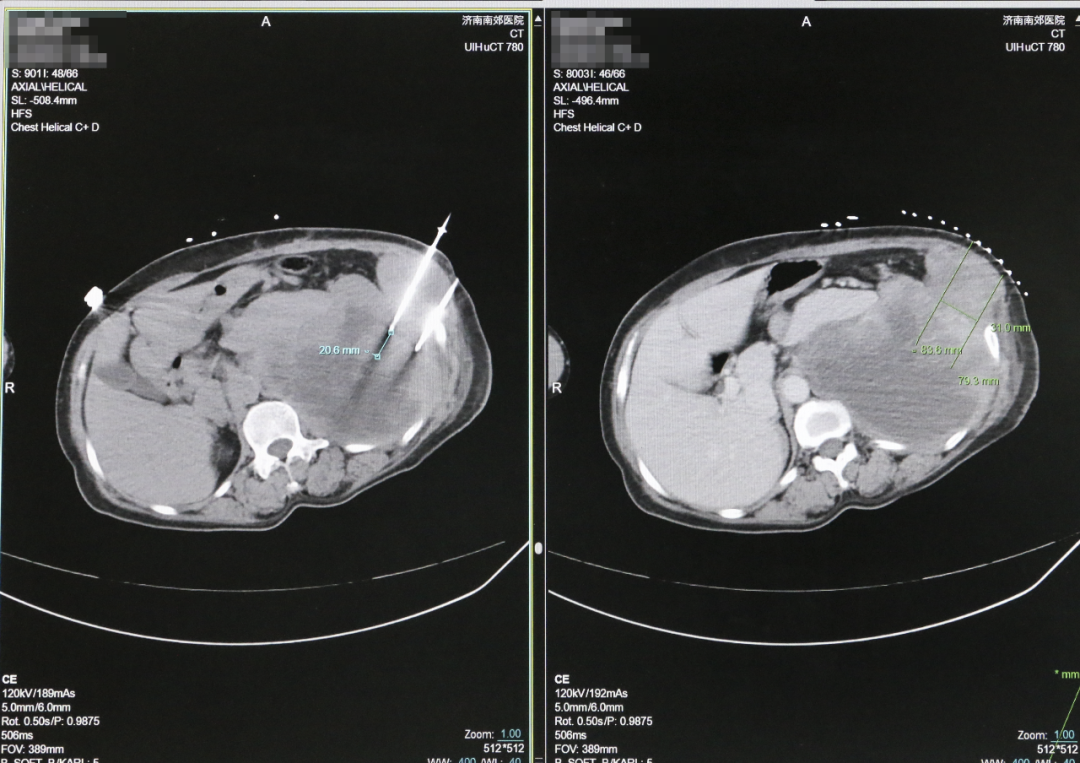

1、精准定位,直捣病灶:在CT引导下,消融针精准穿刺至肿瘤核心,避开周围正常组织;

2、-196℃极速冷冻:液氮瞬间形成“冰晶子弹”,从细胞内部瓦解肿瘤结构;

3、80℃高温复温:冰晶融化引发细胞肿胀破裂,同时高温热效应封闭血管,阻断“癌细胞逃逸通道”。